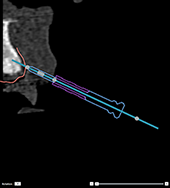

|

Incorrect: the anchor pin is not

anchored into the bone and is not attached to the dental scan.

Template material will not be added around the sleeve. |

|

Incorrect: the anchor pin is not

anchored into the bone, template material is added around the

sleeve but this anchor pin will not provide any fixation during

surgery. |